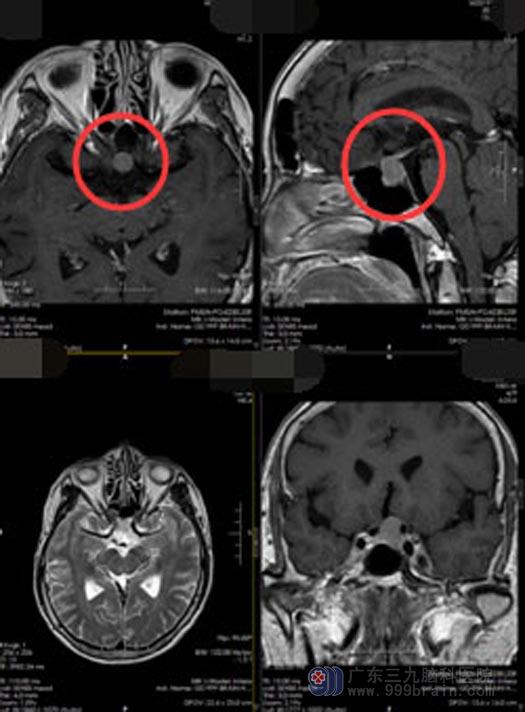

治疗后,陈阿姨头痛头晕等症状不但没有减轻,反而越来越严重。家人感觉有些不对劲,陪同她来到广东三九脑科医院,头颅MR检查提示“垂体前后叶间异常信号影,考虑Rathke囊肿”。鞍区Rathke囊肿是一种先天性的Rathke囊的残留,大多数患者可以没有什么不适症状,对身体也没有什么太大的影响,不需要治疗,如果占位比较大出现了颅内占位症状,垂体受压也可能会出现垂体功能低下、内分泌功能紊乱的表现,就需要考虑手术治疗。

陈阿姨做梦也没想到脑袋里竟然有个肿瘤,家人也认为需要慎重考虑后再决定是否进行手术治疗。回家后,陈阿姨的异常症状越来越严重,她再次来到医院入住神经外五科,陈阿姨的诊断明确,有手术指征,家人同意经鼻蝶行鞍区占位切除术,不开颅就能除掉占位。全麻下行“内镜经鼻蝶鞍区rathke囊肿切除术+颅底重建术”,双侧鼻腔暴露蝶窦开口,切除部分蝶窦粘膜,全层切开硬脑膜,见肿瘤灰白色,质软,正常垂体组织位于前方,囊肿全切,无脑脊液漏,术程顺利。

▲手术前